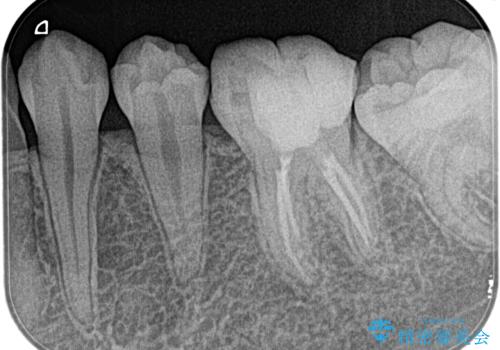

湾曲根管。精密根管治療

担当医 河口智英